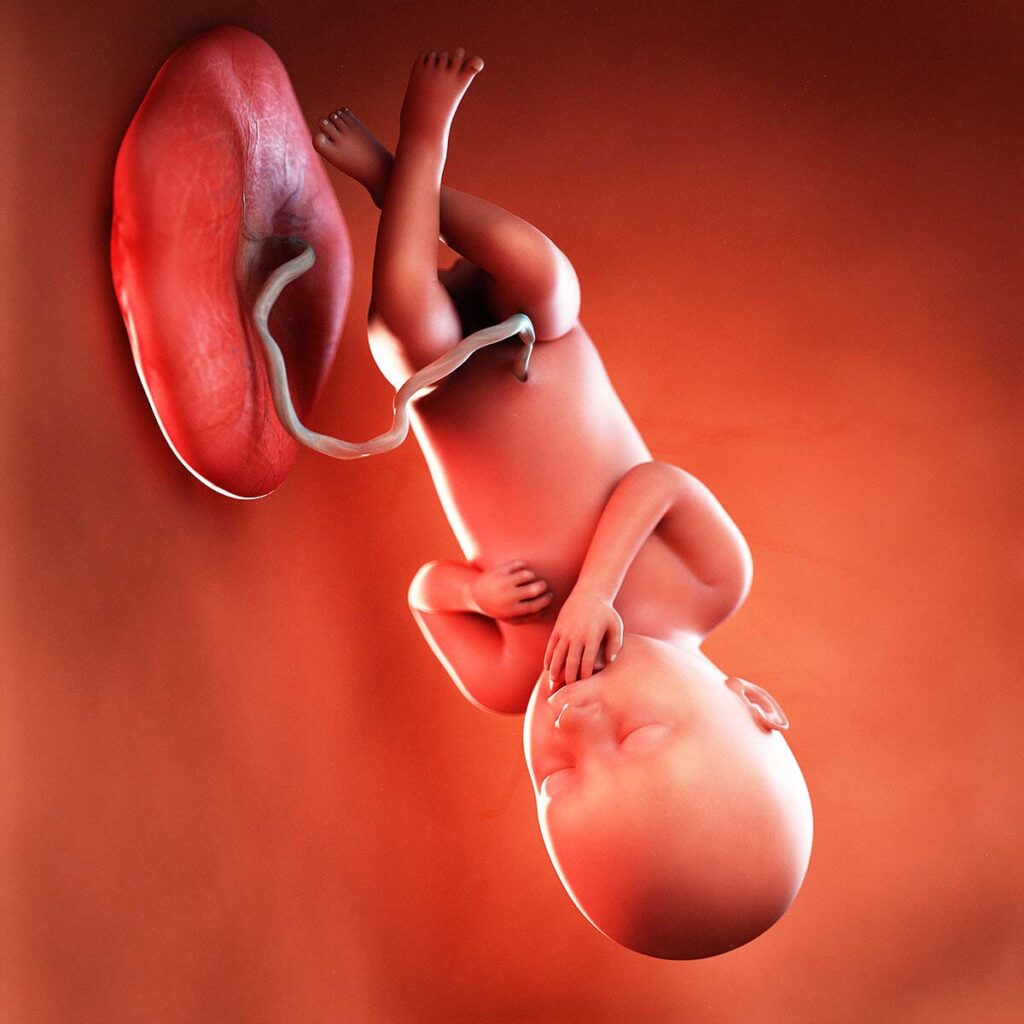

Your baby, or foetus, is around 47.4cm long from head to heel. That’s approximately the size of a romaine lettuce. By now, your baby’s lungs are probably mature enough to breathe outside the womb without any help. Your baby will also be able to suck and digest breast milk.

Actual footage of little TuckMoore yawning.